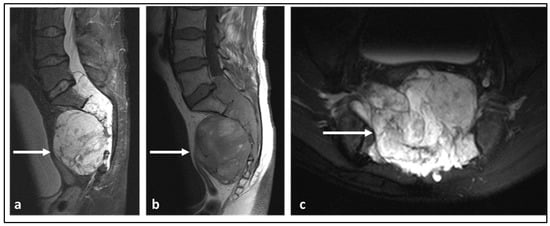

| Chordoma | Low attenuation lytic lesion. | Loculated high T2 signal mass, usually with extra-osseous soft tissue component. High T1 signal due to haemorrhagic and calcified components. |